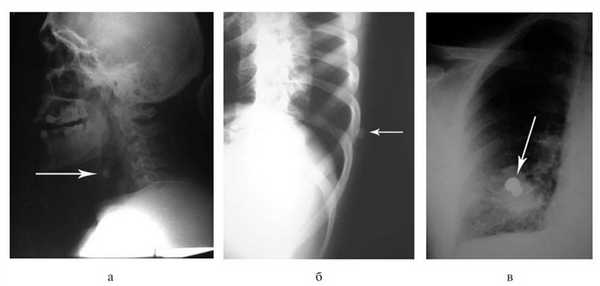

Поверхностные раны шеи требовали первичной хирургической обработки с экономным иссечением их краев. Инородных тел в тканях при этом не выявлено. При глубоком ранении (что определялось по внешнему виду раны) для исключения повреждения органов и структур шеи выполняли обзорную рентгенографию (рис. 4, а), Рисунок 4. Обзорные рентгенограммы пострадавших с ранениями из травматического оружия. Стрелками указаны инородные тела (пули). а - при ранении шеи; б - при непроникающем ранении груди; в - при проникающем ранении груди. затем продольную переднюю колотомию (21 наблюдение). При этом в 1 наблюдении обнаружено ранение трахеи и в 2 - повреждение ротоглотки. Инородные тела извлечены в 10 наблюдениях (пули из пистолета «Макарыч» - в 6, из «Осы» - в 4). Хирургическая обработка раневого канала являлась заключительным этапом вмешательства.

При поступлении пострадавших с ранениями груди и живота, причиненными травматическим оружием, выполняли обзорную рентгенографию. У 217 больных ранения были непроникающими (рис. 4, б). Следует подчеркнуть, что пули калибра 9 мм являются малоконтрастными и определение их локализации при рентгенологическом исследовании представляло определенную трудность.

У 13 раненых огнестрельные повреждения груди были проникающими (рис. 4, в). При отсутствии показаний к торакотомии вмешательство ограничивали первичной хирургической обработкой и дренированием плевральной полости (7 наблюдений). Несмотря на проникающие ранения, при рентгенологическом исследовании инородных тел (пуль) в этих наблюдениях выявлено не было. Двум больным этой группы в отсроченном порядке была выполнена торакоскопия в связи с выявленным инородным телом легкого или плевральной полости на рентгенограмме груди в послеоперационном периоде. В одном из этих наблюдений выполнены пневмотомия и удаление резиновой пули калибра 18 мм, ушивание раны легкого П-образными швами, санация и дренирование плевральной полости. В другом наблюдении резиновая пуля калибра 18 мм лежала в заднем костно-диафрагмальном синусе слева (рис. 5), Рисунок 5. Фотография при торакоскопии: в заднем синусе левой плевральной полости видна резиновая пуля калибра 18 мм. произведены ее удаление, санация и дренирование плевральной полости.